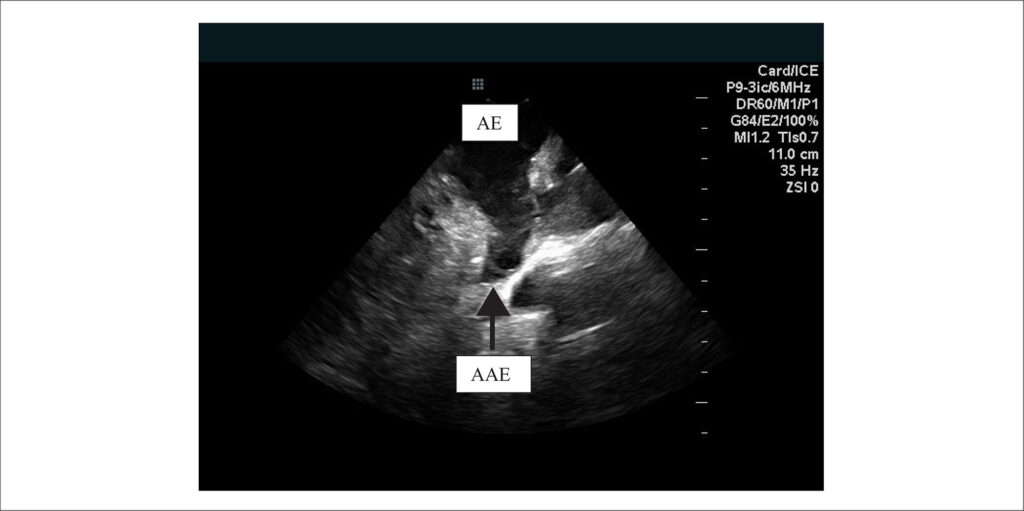

Em casos de FA não valvar quando presentes as referidas contraindicações ao uso dos DOAC a oclusão de apêndice atrial esquerdo (OAAE) se mostra eficaz como alternativa terapêutica. Este procedimento tem sido guiado e realizado pela ecocardiografia transesofágica (ETE) que é considerada como padrão ouro. Porém, serviços que incorporaram a ecocardiografia intracardíaca (EIC) como ferramenta auxiliar durante a ablação por cateter para tratamento da FA passaram a utilizar este método como uma alternativa segura e eficaz ao ETE nos procedimentos de OAAE.–